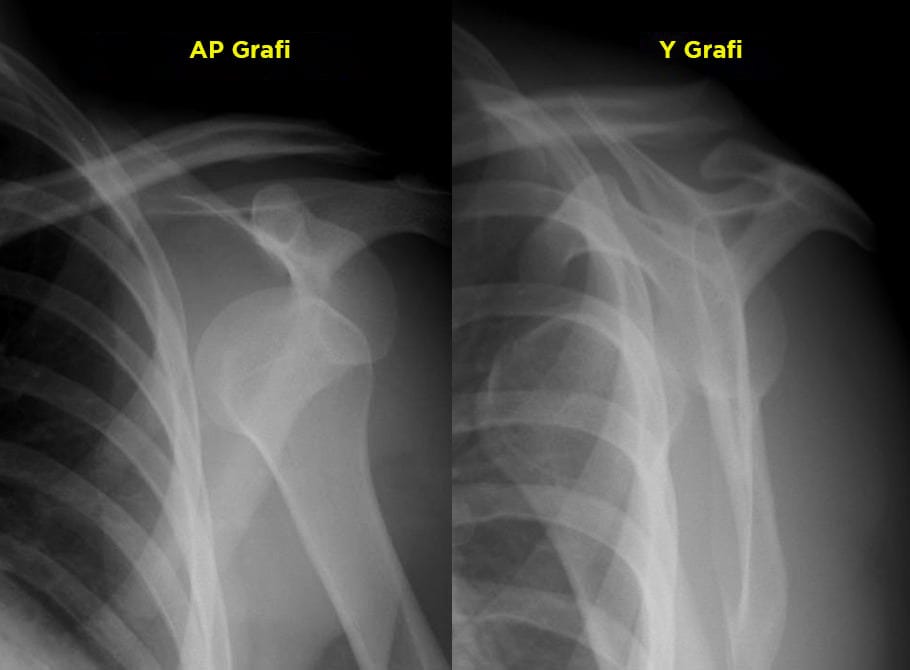

26 yaşında erkek hasta, futbol oynarken düşme sonrasında şiddetli omuz ağrısı nedeni ile acil servise başvuruyor. Hasta öyküsünde maç yaparken travma aldığını ve sonrasında yere düştüğünü, kolunu ağrıdan oynatamadığını belirtiyor. Hasta travma doktoru tarafından; GKS'u 15 Nabız: 80 atım/dk düzenli ; Ateşi 36,7 °C ; Solunum sayısı: 14/dk ; SpO2: 98 ; KŞ: 100 ve Kan Basıncı: 140/90 mm/Hg olarak değerlendiriliyor. Fizik muayenede; sol omuz hareketleri kısıtlı, hareketle ağrılı, omuz anteriorunda ele gelen sert şişlik mevcut, akromiyon lateral kenarı belirgin ayrıca hasta abdüksiyon ve internal rotasyona direnç gösteriyor. Nörolojik muayene normal olarak değerlendiriliyor. Acil hekimi hastadan aşağıda görülmekte olan omuz grafisini istiyor. Bu bilgilere göre bundan sonra hastaya uygulanacak en uygun yaklaşım ne olmalıdır?

Sık görülen çıkık omuz semptomları arasında belirgin omuz ve kol ağrısı, omuz zayıflığı, kol uyuşması ve sınırlı hareket açıklığı bulunur. Omuz öne çıkıklarında yoğun ağrı ve hareketsizlik olur. Humerus başı omuz anteriorunda şişlik olarak gözle görülebilir, palpe edilebilir. Omuzun normal görüntüsü kaybolmuş, omuz oval hattını yitirmiştir. Omuz yuvarlak konturundan yoksundur karemsi bir görünüm almıştır. Akromiyon lateral kenarı belirgindir. Omuzu çıkmış hasta kolunu hafif dış rotasyonda ve diğer eliyle dirsekten destekleyerek hafif abduksiyonda tutarak taşır. Hasta abdüksiyon ve internal rotasyona direnç gösterir.